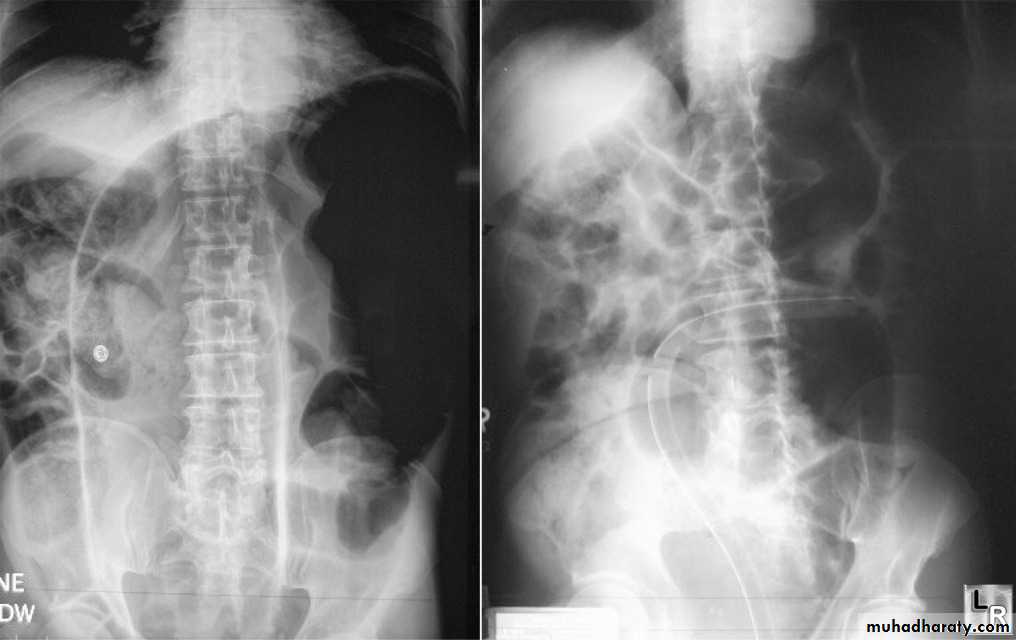

Investigation

Supine abdominal X-ray shows dilated small bowel

May be normal if no air fluid interfaces

Valvulae coniventes differentiate small from large intestine

Erect abdominal film rarely provided additional information